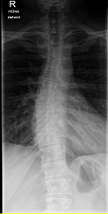

Röntgenbilder

- Dateianhänge

-

- LSPINE

- unbenannt nochmal verkleinert.png (25.52 KiB) 19770 mal betrachtet

deine Bilder lassen vermuten, dass vielleicht gar nicht die Skoliose dein Problem ist, sondern dein sagittales Profil. (Steht dein Kopf ziemlich nach vorne, wenn du dich vin der Seite betrachtest?) solltest auf jeden Fall einmal zum Spezialisten, im deine Situation kompetent abklären zu lassen. Aus NRW ist wahrscheinlich Dr. Verres in Bingen am nächsten.

mit dem sagittalen Profil meint man das Profil von der Seite gesehen. Laut deinen Aufnahmen hast du eher eine geringe Skoliose, aber einen ziemlichen Rundrücken und Hohlkreuz was auch Beschwerden machen kann und das die Ärzte auch gerne übersehen oder nicht sehen wollen. Deshalb ist es auch wichtig, einen Spezialisten aufzusuchen, der dies auch mit behandeln kann. Leider ist dies keine Ganzaufnahme, dann würde man das eher sehen. Es gibt hier schon genug Berichte, die das mit Hyperkyphose und -lordose gut beschreiben. Also lesen bildet...

Dem kann ich mich nur anschliessen, es sieht sehr nach Rundrücken (Bild 2-Hyperkyphose) und Hohlkreuz (Bild 1-Hyperlordose) aus.sloopy hat geschrieben:deine Bilder lassen vermuten, dass vielleicht gar nicht die Skoliose dein Problem ist, sondern dein sagittales Profil.

Zu einer Ganzaufnahme..also beim Orthopäden sah ich eine Ganzaufnahme und sah eine S auf dem Bildschirm. Auf der CD, die ich für den Rheumatologen bekam, ist diese Aufnahme allerdings nicht zu sehen, oder ich verfüge nicht über die notwendigen Programme, um alles zu sehen. Es gab noch drei weitere Bilder, die ich sehen kann und zwar das Becken an sich, was unauffällig ist sowie die rechte Schulter, wo man den Verschleiß deutlich sehen kann.